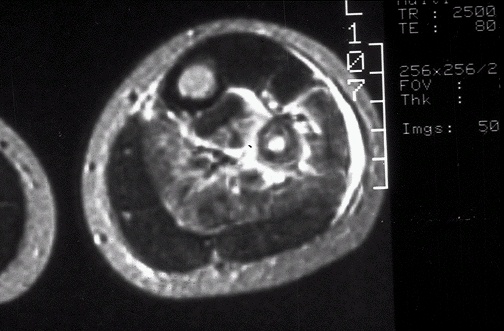

Image 2.2 In this MRI scan in axial (transverse) view through the mid-calf, there is irregular bright extension of the lesion into soft tissue from the bone of the fibula. The normal bone cortex is dark, while normal marrow containing fat is brighter. |